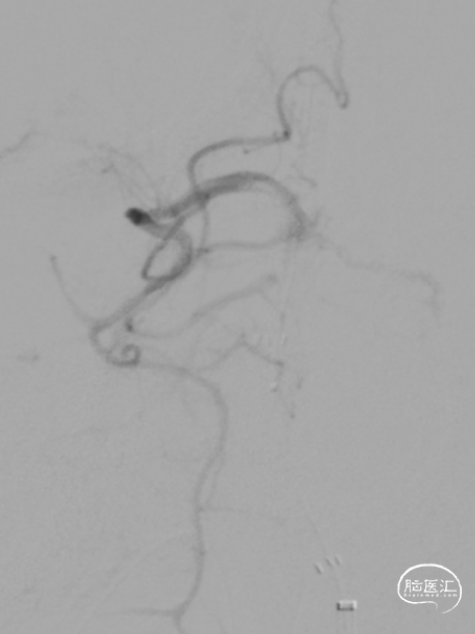

急诊DSA:Ⅱ型弓,基底动脉AICA以远未见显影。

加奇Tethys®中间导引导管到位,明确既往支架位置。但中间导管通过困难。

微导丝微导管通过闭塞段,在右侧大脑后动脉手推造影证实真腔,明确闭塞段,可见造影剂返流至基底动脉尖部,且证明闭塞确为支架内再狭窄导致闭塞。

释放加奇4.0mm*30mm Syphonet®取栓支架,可见支架通体显影。